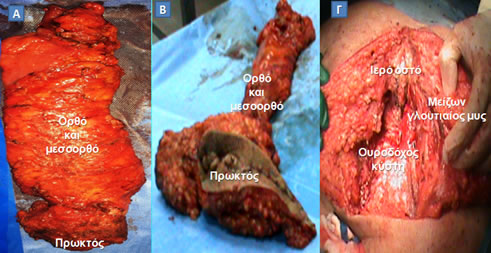

Στην πραγματικότητα, σήμερα, η απόλυτη ένδειξη για τη διενέργεια της «ακρωτηριαστικής» κοιλιοπερινεϊκής εκτομής είναι η άμεση διήθηση των σφιγκτήρων από τον καρκίνο του κατώτερου ορθού, οπότε, αντί της «συμβατικής» κοιλιοπερινεϊκής εκτομής, προτιμάται η ευρεία «εξωανελκτηριακή» κοιλιοπερινεϊκή εκτομή, προκειμένου την πλήρη αφαίρεση του διηθημένου σφιγκτηριακού μηχανισμού και την επίτευξη επαρκούς περιμετρικού ογκολογικού ορίου (Εικόνα 16).

Εικόνα 16.

Α. Χειρουργικό παρασκεύασμα «συμβατικής» κοιλιοπερινεϊκής εκτομής. Β. Χειρουργικό παρασκεύασμα «εξωανελκτηριακής» κοιλιοπερινεϊκής εκτομής. Γ. Περνεϊκό έλλειμμα που απομένει μετά την ευρεία αφαίρεση πρωκτού, ορθοσιγμοειδούς, ανελκτήρων και κόκκυγα (ο ασθενής έχει τοποθετηθεί σε πρηνή θέση), το οποίο καλύπτεται με μυοδερματικό κρημνό από το μείζονα γλουτιαίο μυ.

(Από το προσωπικό αρχείο του Γ. Θεοδωρόπουλου)